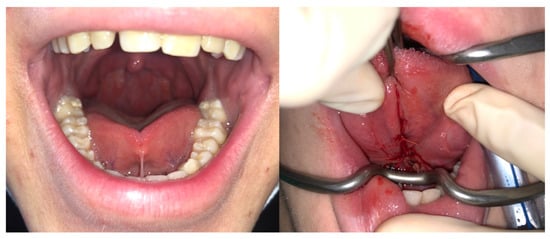

- Amir, L.H.; James, J.P.; Donath, S.M. Reliability of the Hazelbaker assessment tool for lingual frenulum function. Int. Breastfeed. J. 2006, 1, 3. [Google Scholar] [CrossRef] [PubMed] [Green Version]

| Hazlebaker score | 10.79 ± 2.4 | 13.03 ± 1.5 | 0.04 |